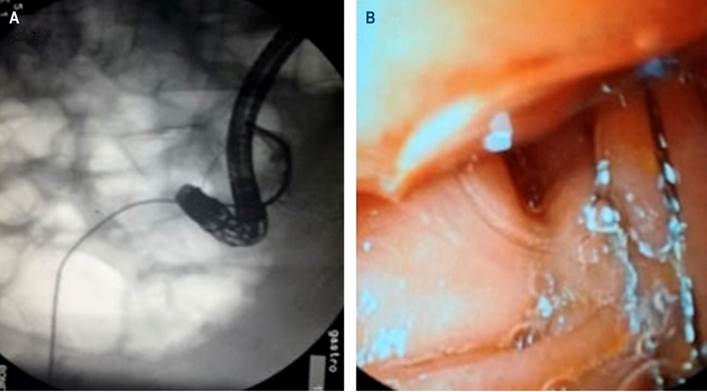

Based on the results, combined instrumentation of the bile duct was carried out by the general surgery and the gastroenterology services through T-tube and endoscopy, respectively. The procedure was performed in the fluoroscopy room, for which a Dormia basket and a mechanical lithotriptor were inserted through the T-tube. As a result, partial fragmentation was achieved, and fragments were advanced into the duodenum.

Also, by the endoscopic route, stones were fragmented and extracted by means of a Dormia basket (Figure 3) and an extraction balloon. A cholangiography was performed using the T-tube, and an adequate passage of the contrast agent into the duodenum was observed, without extravasation, nor evidence of residual stones (Figure 2B).

Figure 3 A. Combined instrumentation fluoroscopy. B. Duodenoscopic view of the Dormia basket inserted through the T-tube.